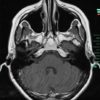

U dây VIII - Ảnh 4

U dây VIII

» Thông tin: Nữ giới – 35 tuổi.

» Lâm sàng: Điếc đột ngột.